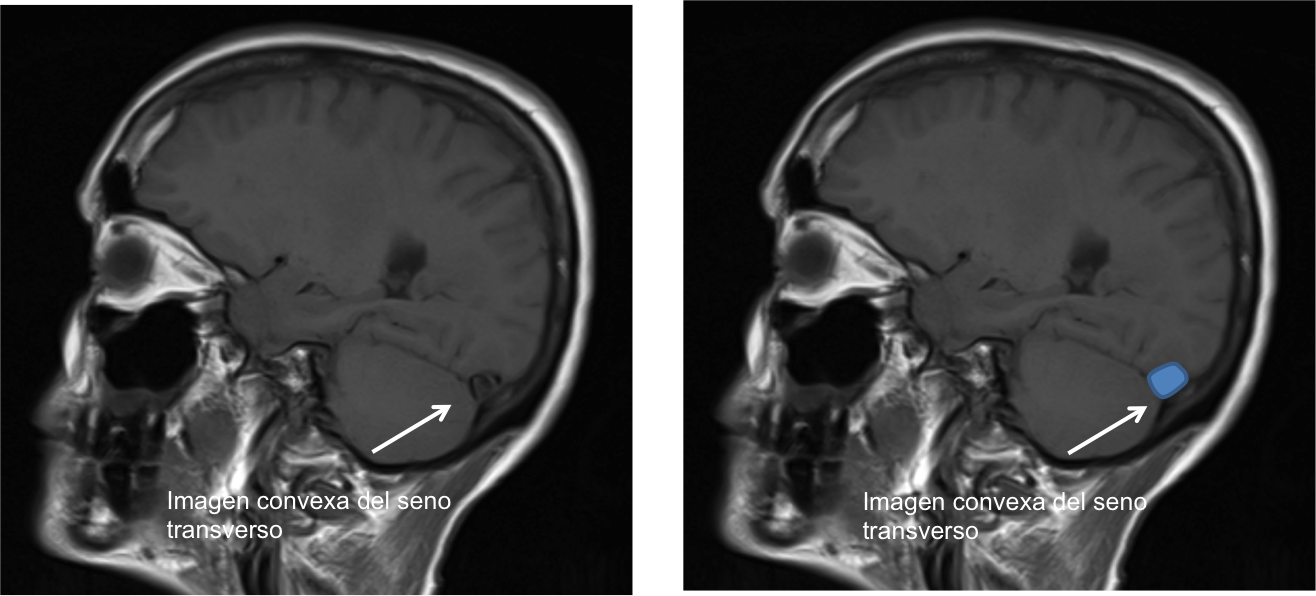

En la Imagen 4 y 5 podemos ver el aspecto congestivo y redondeado de los senos venosos longitudinal y transverso.

En la Imagen 8, podéis observar el signo de distensión venosa descrito en casos de hipotensión intracraneal que se refiere a un cambio de la morfología del margen inferior de la porción media del seno transverso que adquiere una morfología convexa.